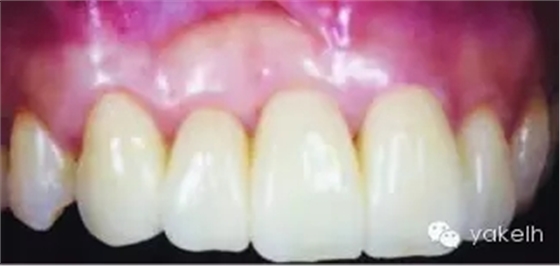

¤¤這類復(fù)雜的膜齦手術(shù)用于同時(shí)處理多個(gè)根面Ⅰ類/使Ⅱ類牙齦退縮(圖5.11a~m)。

圖5.11 (a)患者休息放松狀態(tài)下的嘴唇——上下唇不能完全閉合。(b)右上尖牙和側(cè)切牙呈Ⅰ類牙齦退縮。(c)左上頜尖牙和側(cè)切牙呈Ⅱ類牙齦退縮。(d)先用圓形眼科刀片開始做溝內(nèi)切口。(e)使用探針在袋內(nèi)垂直探查貫通隧道,越過膜齦聯(lián)合。(f)使用探針在隧道內(nèi)橫向探查貫通,保留齦乳頭尖端附著于骨面。(g)從腭部取結(jié)締組織移植物,使用絲線牽引,將厚度和大小足夠的結(jié)締組織瓣插入隧道內(nèi)。(h)通過懸吊縫合將組織瓣冠向復(fù)位,穩(wěn)定結(jié)締組織瓣。(i)術(shù)后6個(gè)月,上頜右側(cè)觀。(j)上頜左側(cè)觀,可見牙齦厚度以及色澤的協(xié)調(diào)性均得到改善。(k)術(shù)后6個(gè)月正面觀,牙敏感癥狀消失。(l)術(shù)后1年的全口影像,顯示雙側(cè)的牙齦退縮均被完全覆蓋,牙齦邊緣增厚且穩(wěn)定,與釉牙骨質(zhì)界輪廓一致,也與左側(cè)中切牙釉質(zhì)缺損輪廓一致。(m)患者嶄新的笑容,可見側(cè)切牙及尖牙的齦緣無退縮。